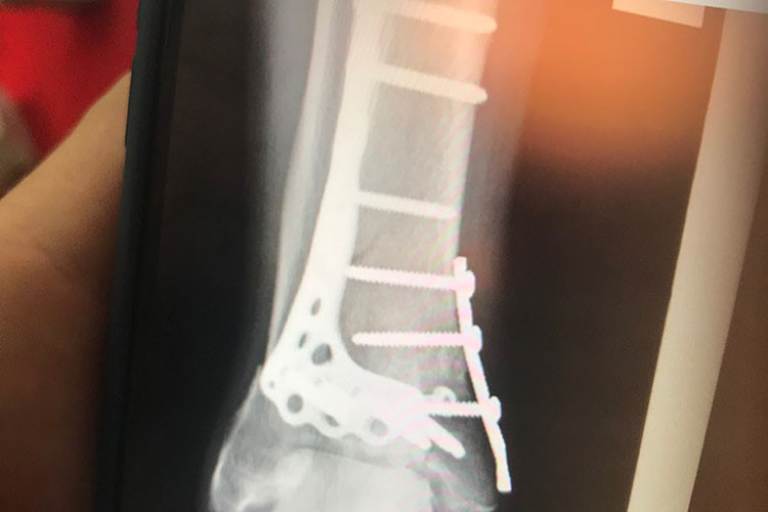

Was Cal Crutchlow seit seinem Crash im zweiten freien Training auf Phillip Island Ende Oktober 2018 erleiden musste, spottet jeder Beschreibung. Der Engländer stürzte damals in Kurve 1 mit rund 260 km/h und zerschmetterte seinen rechten Innenknöchel, das Sprungbein und das Distalende des Schienbeins. Anfang Februar saß er in Malaysia zum ersten Mal wieder auf dem Motorrad, beim Saisonstart Anfang März in Katar brauste der Engländer auf Platz 3!

In der Weltmeisterschaft liegt Crutchlow nach 4 von 19 Rennen vor Le Mans am kommenden Wochenende mit 27 Punkten auf Gesamtrang 9. Beim Fahren merkt man es ihm nicht an, aber schmerzfrei ist der 33-Jährige nicht. Das Sprungbein war in 17 Teile zerbrochen, die große Metallplatte auf der Rückseite des Knöchels stößt fast durch die Hautoberfläche. Insgesamt befindet sich fast ein Kilogramm Leichtmetall in seinem Knöchel. "Ich habe jetzt mehr Probleme mit dem Knöchel und den Nerven im Fuß, als zu Saisonbeginn", erzählte Crutchlow. "Mit den Ärzten sprach ich schon darüber, das Metall zu entfernen – wahrscheinlich aber erst zum Ende des Jahres." Sein Problem: Traditionell ist am Dienstag und Mittwoch nach dem letzten Rennen der Saison Ende November der Test in Valencia, danach wird es einen weiteren in Jerez geben. "Letztes Jahr waren sich alle Fahrer bis auf Tito Rabat einig, dass sie nach der Saison in Urlaub wollen, jetzt müssen wir auch noch in Jerez fahren", schimpfte Crutchlow. "Ich will ins Krankenhaus, um mich operieren zu lassen, dafür brauche ich zehn Tage frei, ich muss aber testen. Die Fahrer waren sich einig, die Teams haben uns aber überstimmt. Wir werden alle unsere Teams darum bitten nicht zu testen, aber das wird nicht passieren."